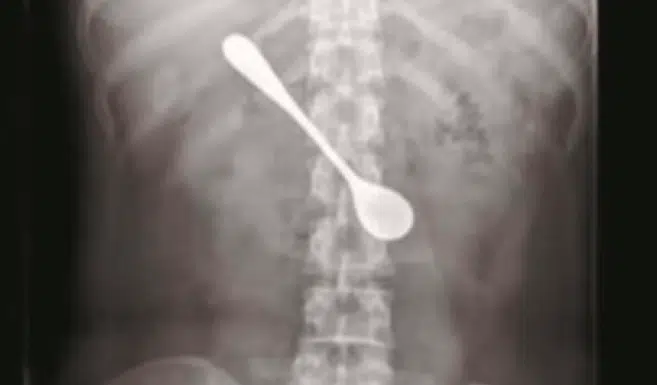

On vous parlait de cette jeune femme qui était restée paralysée à cause d'un geste que nous faisons tous. Cette fois-ci, on vous parle de cette femme qui a avalé une cuillère en essayant de déloger une arête coincée dans sa gorge. Malgré plusieurs tentatives, cette Chinoise n'a pas réussi à déloger l'arête. Elle s'est alors servie d'une cuillère pour retirer l'arête, jusqu'à ce que cela tourne au drame. Elle a finalement avalé l'ustensile ! Mais au lieu de vite se rendre aux urgences, elle est restée pendant 4 jours avec la cuillère de 13 cm dans son estomac. En réalité, elle avait peur de ne pas pouvoir assister au festival de Quingming.

Finalement, la jeune femme s'est rendue à l'hôpital. Après plusieurs examens, les médecins ont décidé de l'opérer en urgence. Pendant l'opération, les médecins ont dû redresser la cuillère qui était légèrement inclinée, afin de pouvoir la retirer à la verticale. Avaler une arête n'est pas anodin. Même si les complications sont rares il est important de toujours se rendre chez un médecin si celle-ci reste coincée trop longtemps. Heureusement, cette jeune femme s'en est sortie saine et sauve !